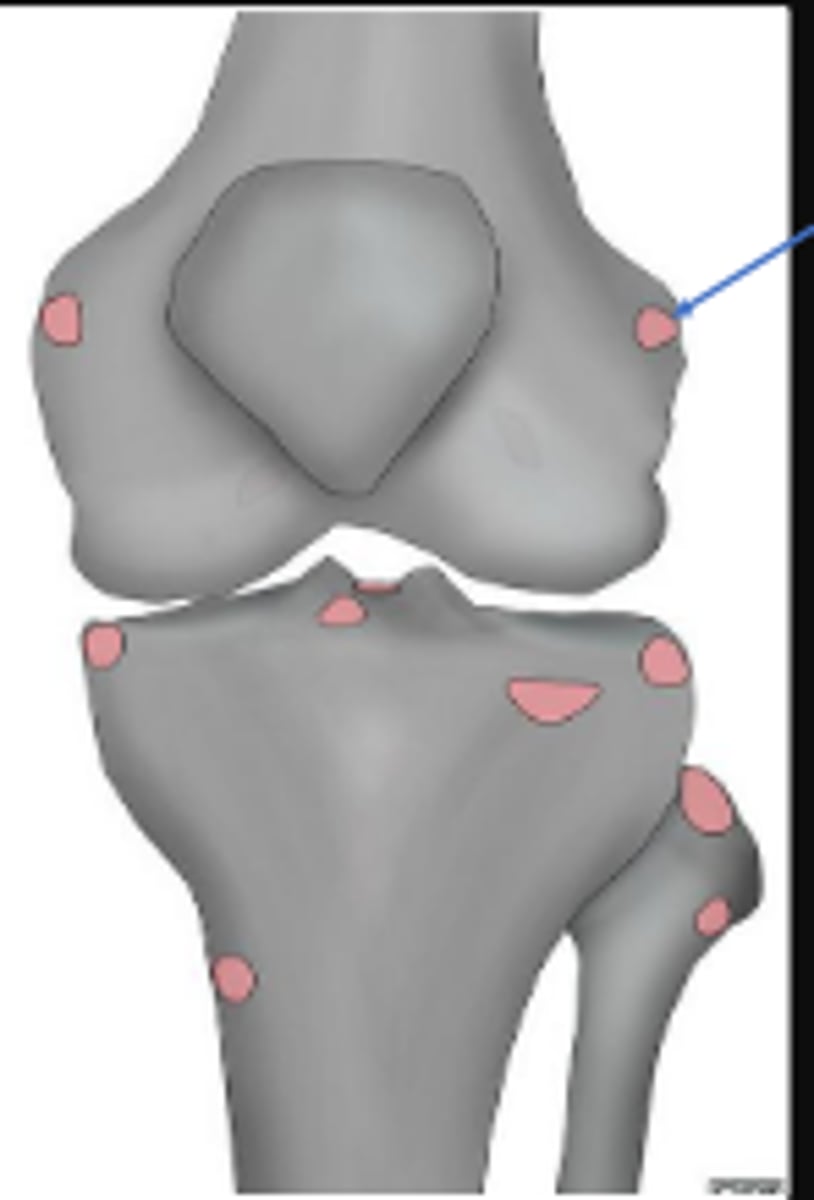

Right adductor tubercle

What tubercle is pointed to by the arrow?

Lateral epicondyle of the right femur

What is the arrow pointing to?

Medial epicondyle of the right femur